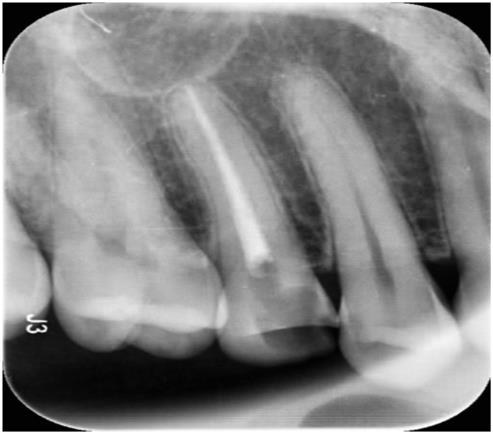

신경치료

치아가 많이 썪은 경우 신경치료를 하고 치아를 살릴 수 있습니다.